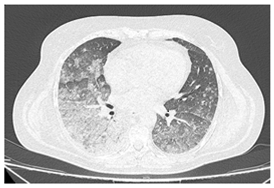

| Type of SARD-ILD | HRCT Features | Axial HRCT Images in Patients with SARD-ILD | Description of HRCT Images in Patients with SARD-ILD |

|---|---|---|---|

| RA-ILD | UIP; NSIP; airway disease with obliterative and follicular bronchiolitis; rheumatoid nodules. | ![]() | UIP, specific to RA-ILD, is characterized by traction bronchiectasis, which may present as subpleural fibrotic cysts with a “honeycomb” appearance, overlapping in multiple layers. UIP often represents the final stage in the progression of most connective tissue diseases and is associated with the most severe prognosis. |